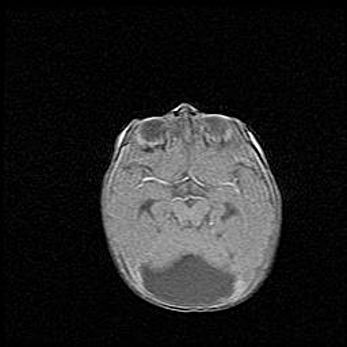

Открытая гидроцефалия.

Возраст: 9 месяцев 12 дней

Вес: 6800 г

Пол: мужской

Окружность головы: 41,5 см

Срок гестации: 28 недель

Гидроцефалия головного мозга у новорожденных имеет характерный признак: опережающий рост окружности головы приводит к визуально хорошо определяемой гидроцефальной форме сильно увеличенного в объёме черепа. Детские неврологи определяют следующие симптомы гидроцефалии у грудничков: выбухающий напряжённый родничок, частое запрокидывание головы, смещение глазных яблок к низу.